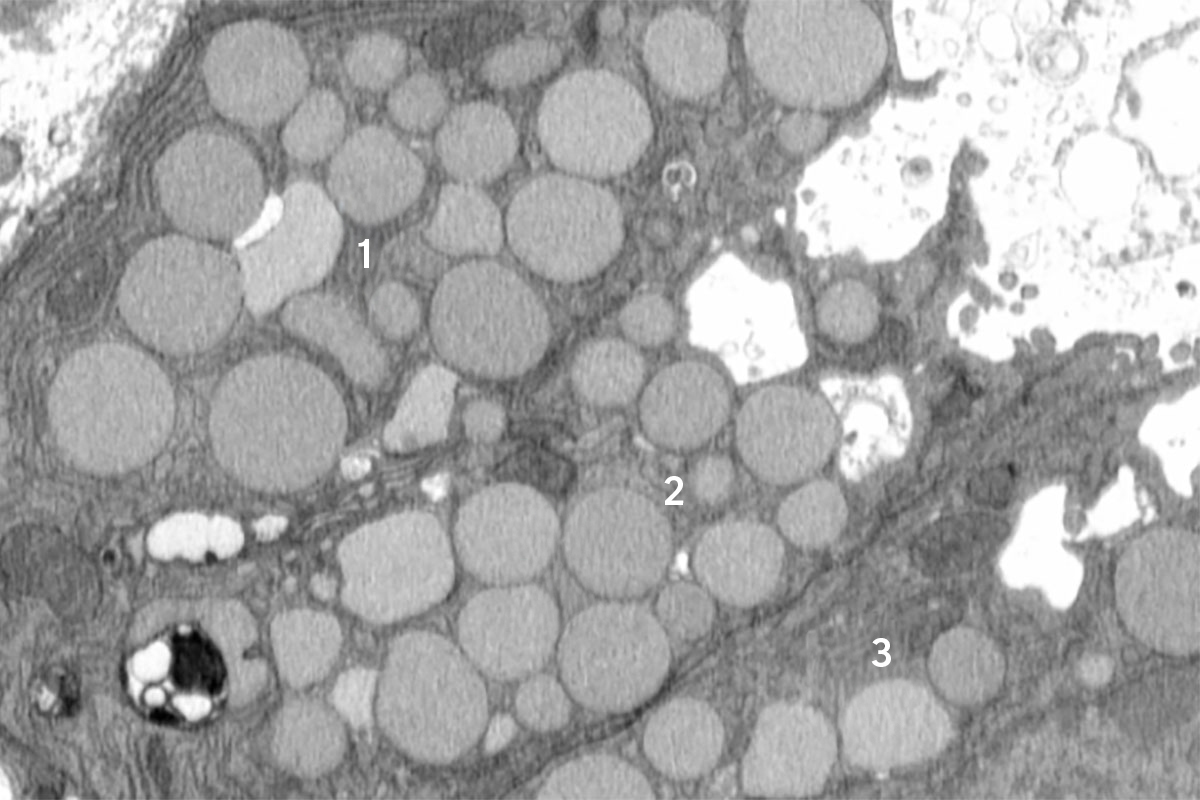

Now, a new study in mice led by researchers at Washington University School of Medicine in St. Louis and the Baylor College of Medicine reveals a previously unknown cellular purging process that may help injured cells revert to a stem cell-like state more rapidly. The investigators dubbed this newly discovered response cathartocytosis, taking from Greek root words that mean cellular cleansing.

Published online in the journal Cell Reports, the study used a mouse model of stomach injury to provide new insights into how cells heal, or fail to heal, in response to damage, such as from an infection or inflammatory disease.

“After an injury, the cell’s job is to repair that injury. But the cell’s mature cellular machinery for doing its normal job gets in the way,” said first author Jeffrey W. Brown, MD, PhD, an assistant professor of medicine in the Division of Gastroenterology at WashU Medicine. “So, this cellular cleanse is a quick way of getting rid of that machinery so it can rapidly become a small, primitive cell capable of proliferating and repairing the injury. We identified this process in the GI tract, but we suspect it is relevant in other tissues as well.”

Brown likened the process to a “vomiting” or jettisoning of waste that essentially adds a shortcut, helping the cell declutter and focus on regrowing healthy tissues faster than it would be able to if it could only perform a gradual, controlled degradation of waste.

In paligenosis, injured cells shift away from their normal roles and undergo a reprogramming process to an immature state, behaving like rapidly dividing stem cells, as happens during development. Originally, the researchers assumed the decluttering of cellular machinery in preparation for this reprogramming happens entirely inside cellular compartments called lysosomes, where waste is digested in a slow and contained process.

From the start, though, the researchers noticed debris outside the cells. They initially dismissed this as unimportant, but the more external waste they saw in their early studies, the more Brown began to suspect that something deliberate was going on. He utilized a model of mouse stomach injury that triggered the reprogramming of mature cells to a stem cell state all at once, making it obvious that the “vomiting” response — now happening in all the stomach cells simultaneously — was a feature of paligenosis, not a bug. In other words, the vomiting process was not just an accidental spill here and there but a newly identified, standard way cells behaved in response to injury.